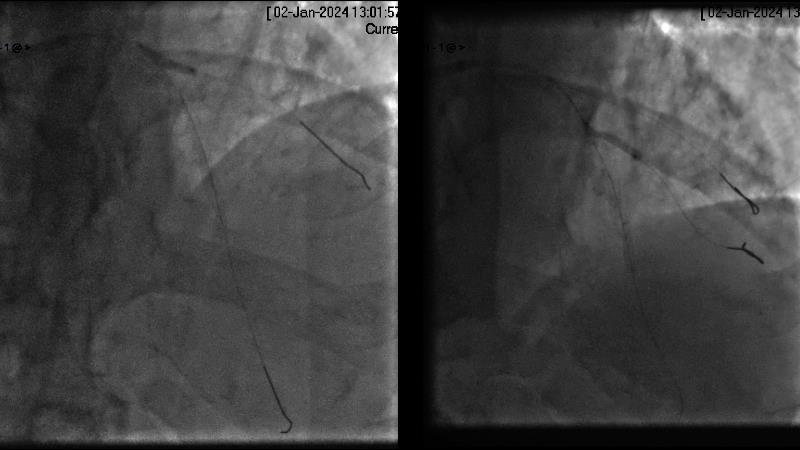

Browse this EuroPCR 2024 session to explore the safety and efficacy of sirolimus-coated balloons from pre-clinical data, review MagicTouch data from real-world populations with case-based examples, and learn about the MagicTouch sirolimus-coated balloon clinical programs. Discover insights and takeaways from the significance of the EASTBOURNE subgroups, and analyze the challenges and opportunities in PCI for diabetic patients.

- To learn from the real world registries and complex cases to understand the practical implications and potential of the device in diverse patient population